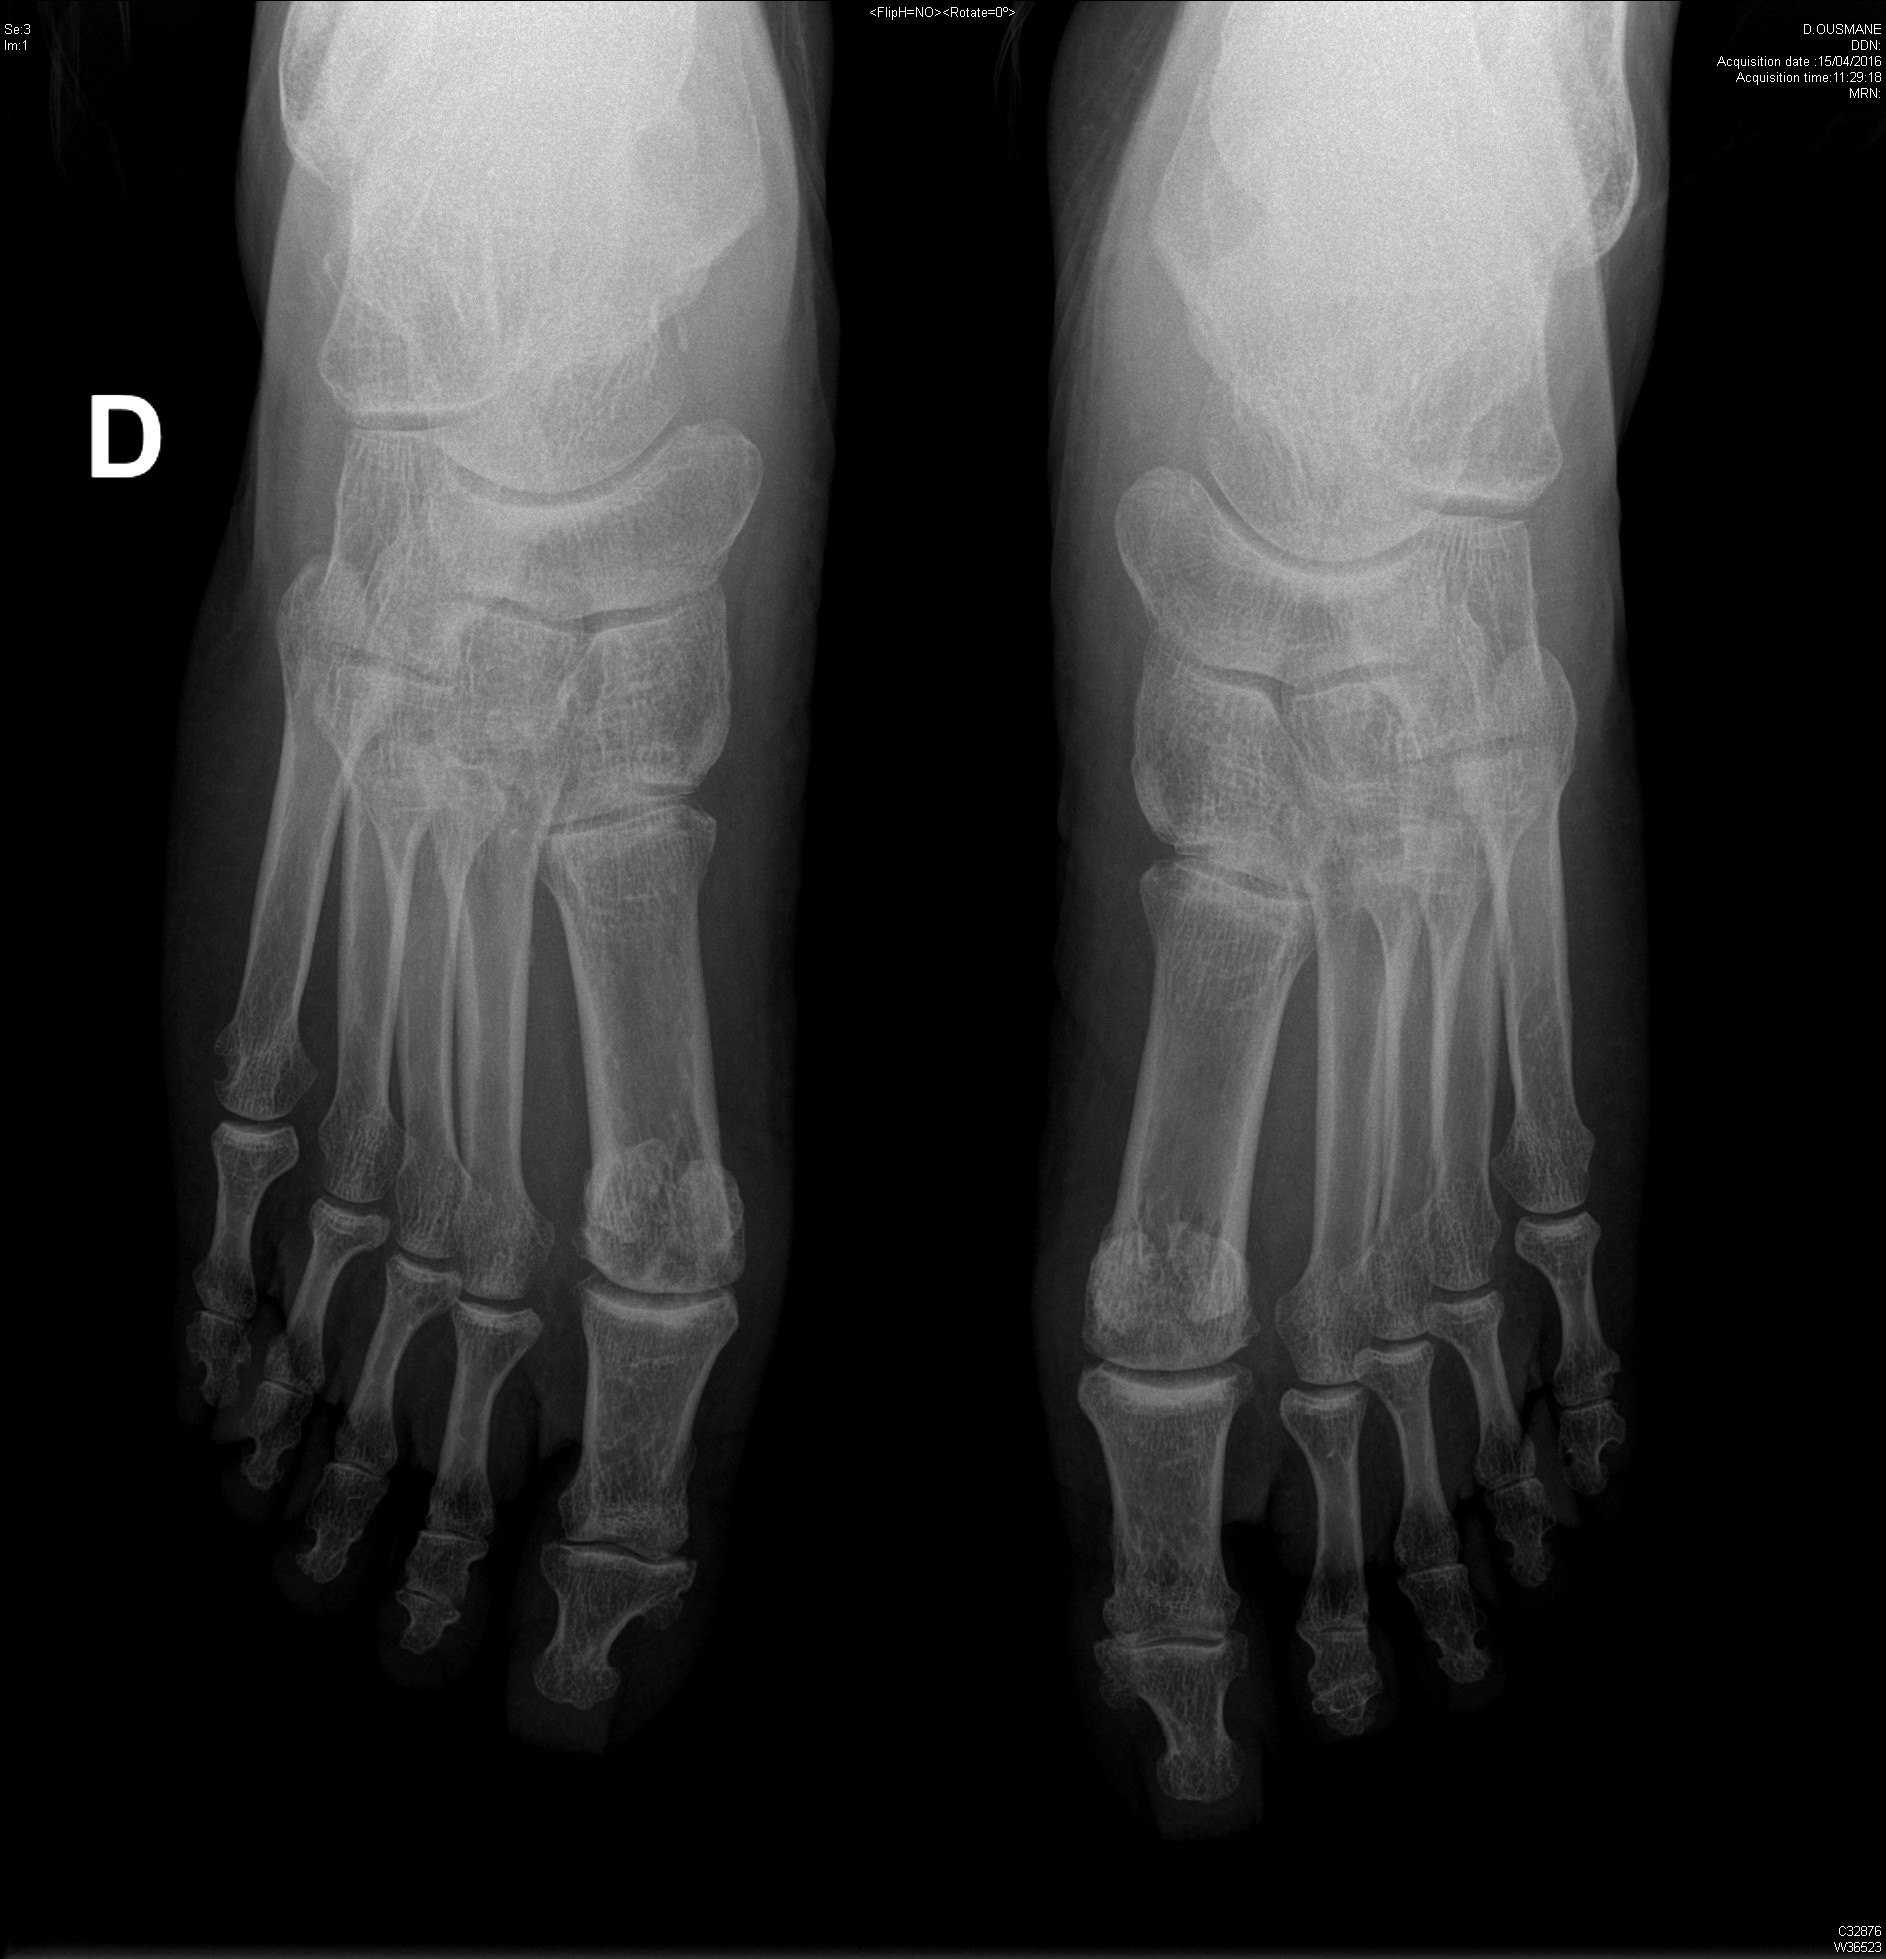

Polyarthrite rhumatoïde séropositive, sévèrement érosive aux pieds